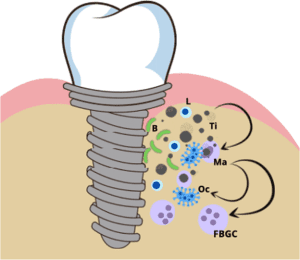

حساسیت بیش از حد، دنباله ای از واکنش های نامطلوب توسط سیستم ایمنی بدن است. نوع و نحوه ایجاد آنها ممکن است متفاوت باشد. آنها به طور کلی به چهار گروه (I-IV) طبقه بندی می شوند. حساسیت بیش از حد به فلز معمولاً یک حساسیت بیش از حد نوع IV است که به عنوان واکنش حساسیت بیش از حد تأخیری شناخته می شود، زیرا ایجاد واکنش 48 تا 72 ساعت طول می کشد. اولین تماس با یک آنتی ژن فلزی باعث مصرف آنتی ژن (توسط سلول های دندریتیک لانگرهانس) و ارائه آنتی ژن به لنفوسیت های TH می شود. لنفوسیت های TH منشأ خود را در تیموس دارند و به تولید سیتوکین هایی هدایت می شوند که مسیرهای پاسخ ایمنی را تنظیم می کنند. اگر بیمار دوباره در معرض آنتی ژن فلزی قرار گیرد، لنفوسیت های TH ماکروفاژها را فعال می کنند. از این رو، التهاب برای مقابله با تهدید درک شده القاء می شود. پاسخ ایمنی ممکن است منجر به آسیب بافتی و در نهایت از دست دادن ایمپلنت در شرایط استریل شود.

قرار گرفتن در معرض فلزات ناشی از ایمپلنت های دندانی اندوسئوس endosseous ، پرکننده های آمالگام یا پروتزهای مفصلی می تواند منجر به مشکلات جدی سلامتی شود. سوء ظن منطقی به حساسیت بیش از حد به فلز می تواند امکان آزمایش در بیماران حساس را با استفاده از روش سنجش تحریک ایمنی لنفوسیت حافظه، که به عنوان آزمایش MELISA شناخته می شود، فراهم کند. این یک آزمایش خون برای تشخیص حساسیت بیش از حد به فلز است. لنفوسیت های TH از نمونه های خون جدا شده و بر اساس میزان قرار گرفتن بیمار در معرض فلزات انتخاب شده آزمایش می شوند. از شاخص تحریک برای اندازه گیری واکنش پذیری بیمار به فلزات مختلف استفاده می شود. MELISA بویژه در بیمارانی که علائم آلرژی به فلز (خستگی مزمن، درد مزمن مفاصل، درماتیت تماسی و واکنش های لیکنوئید دهانی) دارند اما آزمایش های پچ منفی داشته اند، مفید است.